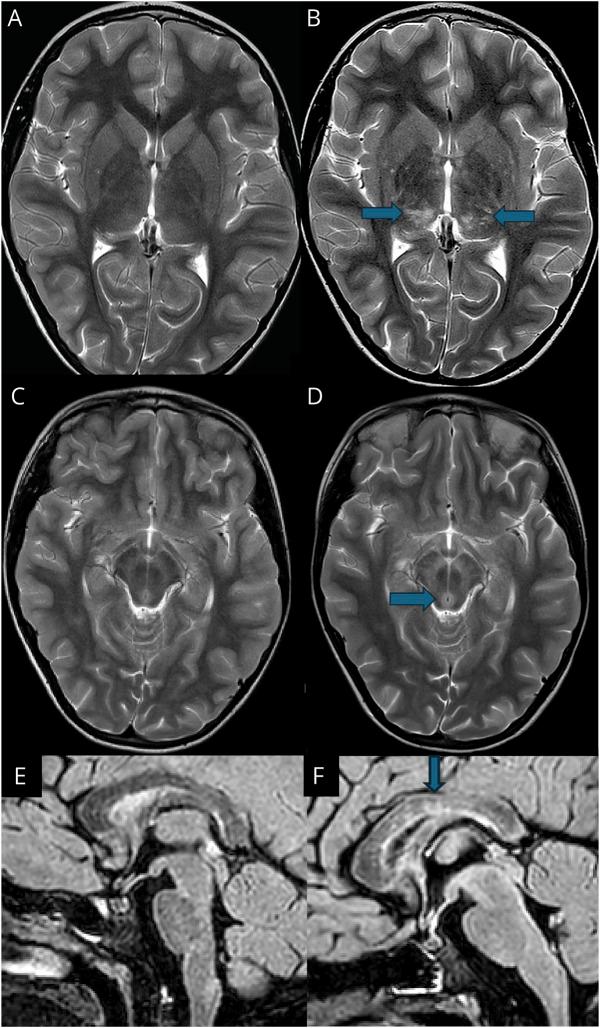

We identified and included 15 children (5 girls, 10 boys). The median age at onset was 9.9 years (range: 2-16 years). All children presented with features of AE or meningitis, acute cerebellitis, or transverse myelitis. CSF pleocytosis was common (13/15, median 245 cells/μL), and 13 (87%) of 15 harbored GFAP-abs in their CSF, 8 (53%) of whom did not have detectable GFAP-abs in their serum. MRI was abnormal in 15 (100%) of 15 children: Specific patterns included confluent lesions in the pons or caudate nucleus (11/15; 73%), peri-aqueductal regions (13/15; 87%), and spinal cord (6/10; 60%). 12 children had a favorable outcome (mRS score of </= 1). Two patients died in the acute phase or during follow-up.

我们确定并纳入了 15 名儿童(5 名女孩,10 名男孩)。发病中位年龄为 9.9 岁(范围:2-16 岁)。所有患儿均表现为 AE 或脑膜炎、急性小脑炎或横贯性脊髓炎的特征。CSF 细胞增多症常见(13/15,中位数 245 个/μL),15 名患儿中有 13 名(87%)的 CSF 中存在 GFAP-abs,其中 8 名(53%)患儿血清中未检测到 GFAP-abs。15 名患儿的 MRI 异常(100%):特定模式包括桥脑或尾状核的融合性病变(11/15;73%)、导水管周围区域(13/15;87%)和脊髓(6/10;60%)。12 名患儿预后良好(mRS 评分<=1)。2 名患儿在急性期或随访期间死亡。